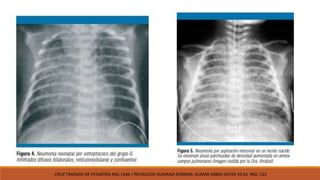

FISIOPATOLOGÍA: 3 procesoshistopatológicos. FORMACIÓN DE MEMBRANA HIALINA • Respuesta inespecífica asociada a deficiencia de surfctante. • Daño a epitelio alveolar. • Se observa en neumonías del grupo B • Perdida de permeabilidad de capilare alveolares. INFLAMACIÓN SUPURATIVA • Necrosis del parénquima • Formación de microabcesos y obstrucción parcial. • Principales agentes causantes: S. Aureus, Bacilos entéricos (k. pneumoniae, E. Coli, psudomona, hongos) NEUMONITIS INTERSTICIAL • Inflamación intersiticial • Edema • Infiltrado mononuclear • Exudado seroso Avery Neonatología Diagnóstico y tratamiento del Recién nacido 7ª Edición. Mhairi g. McDonald

CONGESTIÓ N: • Exudado • Bacteriasen alveolos HEPATIZACI ÓN ROJA • Eritrocitos • Leucocitos • bacterias HEPATIZACI ÓN GRIS • Lisis y degradación de eritrocitos. • Neutrófilos • Eliminación de bacterias RESOLUCIÓ N • Presencia de macrófagos. • Eliminación de restos de neutrófilos, bacterias y fibrina • Cede la inflamación HISTOPATOLOGÍA CRUZ TRATADO DE PEDIATRÍA PAG 1446 / PATOLOGÍA HUMANA ROBBINS. KUMAR ABBAS ASTER 10 Ed. PAG: 522